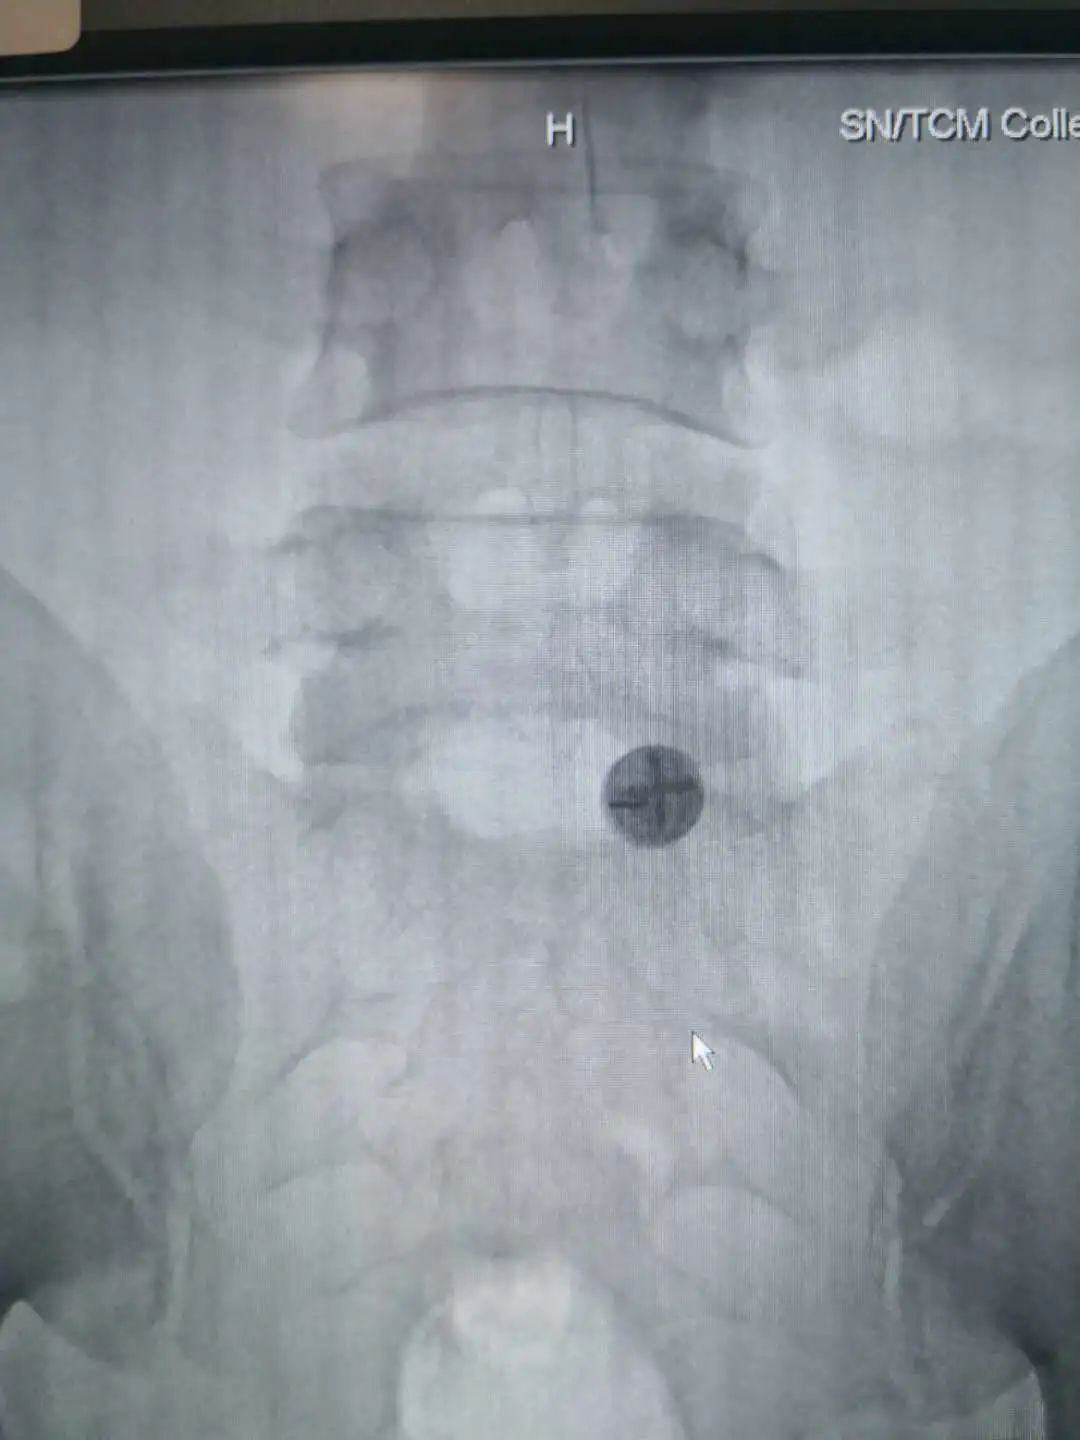

患者入院后,科室给予保守治疗,但症状缓解不明显。医院副院长寇久社、科室副主任张保平及相关医护人员对病情进行多次讨论后,一致认为患者疼痛为腰椎间盘突出神经根受压所致,拟行手术治疗。但患者年纪较轻,家属拒绝进行开放手术。经仔细评估及与患者家属充分沟通后,科室决定对他实施椎板间入路内镜下脱出髓核摘除术。

术前讨论中,科室充分考虑到患者生命体征、年龄及心理等因素,针对手术过程中心、肺、脑等重要脏器可能出现的各种意外,也制定了充分的应急预案。手术顺利完成,术后患者安返病房, VAS疼痛评分稳定在0-1分,当天夜里就可以安静入睡,术后第1天就可以下床行走了,腰腿疼痛明显缓解,生活质量得到很大提高。